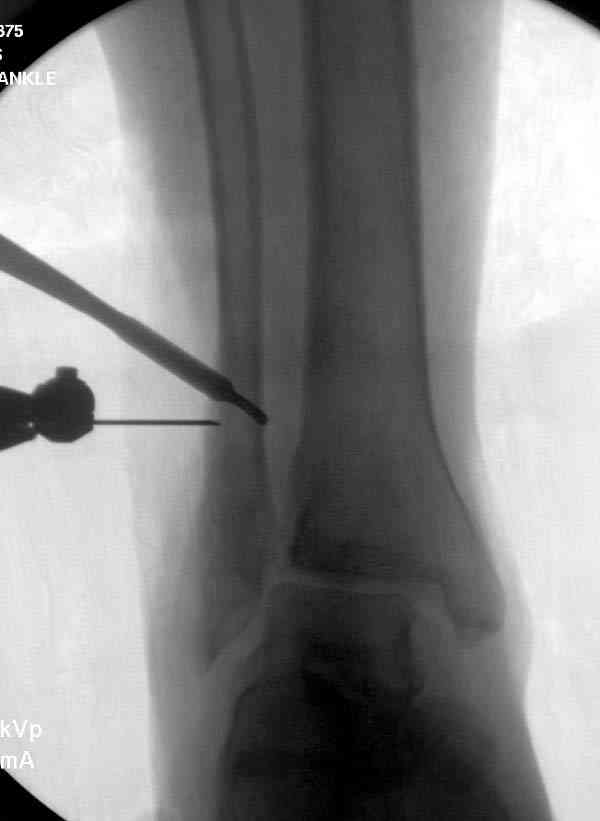

Здесь представлено решение похожей проблемы. Больной в течение года лечился консервативными мерами, и боли в голеностопе были основным показанием к операции.

Проведена обычная стандартная процедура по исправлению неудовлетворительного состояния голеностопного сустава, где кроме удлинения малоберцовой с применением compression tension device за проксимальный конец пластины, проведено замещение трикортикальным графтом из крыла, освобождение синдесмоза и медиальной щели от

фибротических масс с фиксацией.

Дополнительно у больного плоская стопа, во время операции провели небольшую скользящую остеотомию, надеемся, что поможет.